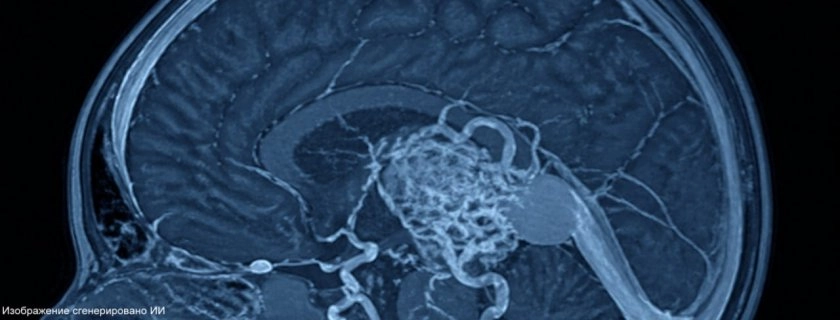

У малыша выявили опасное нарушение в работе сосудов мозга - артериовенозную мальформацию вены Галена, из‑за которой сердце испытывает сильную перегрузку, а тонкие сосуды в голове могут прорваться в любой момент. Единственным шансом для таких пациентов становится эндоваскулярная эмболизация: во время вмешательства хирурги "склеивают" патологические сосуды спиралями или полимерами.

26 апреля в клинике Педиатрического университета ребенку успешно провели эндоваскулярное вмешательство, которое должно снять критическую нагрузку с сердца и защитить сосуды мозга. Медики продолжают наблюдать за состоянием малыша.